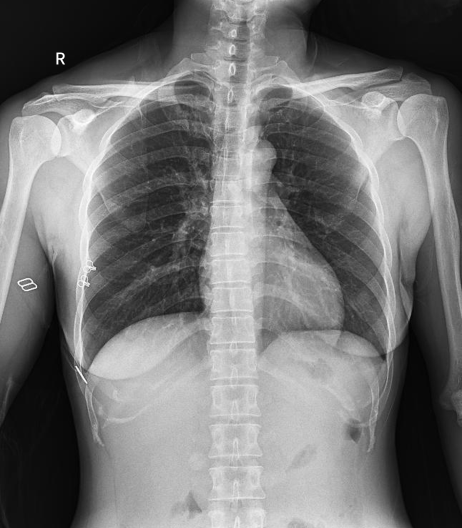

球管傾斜攝影角度-45°~45°,滿足臨床各部位各角度的攝影需求。如:髕骨軸位、頸椎正位、骶尾椎、鼻竇瓦氏位、梅氏位等部位檢查。

拉伸自如:SID電動拉伸,最長可延伸至1.8米,滿足放射科室各種拍片距離的需求。如:GBZ 70-2015職業(yè)性塵肺病的診斷標準中對胸片拍片距離1.8米的要求。